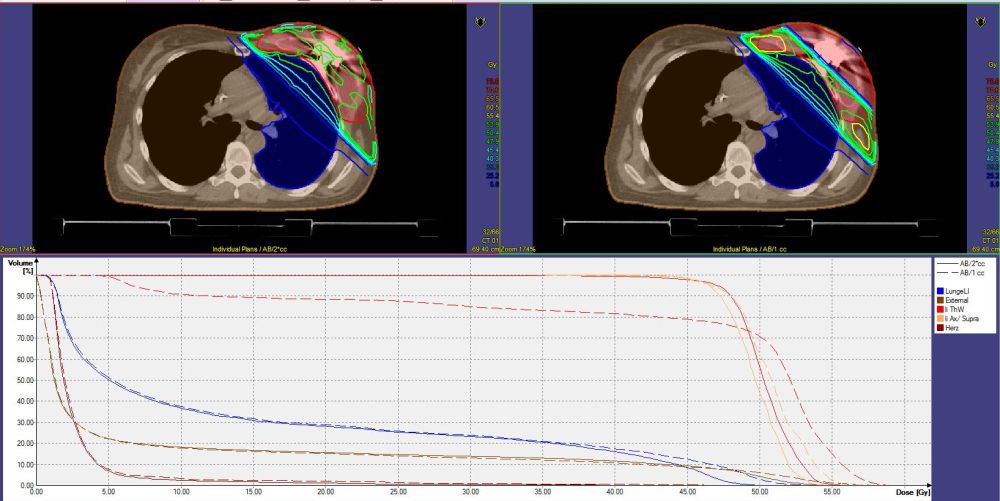

| Dosimetrie | Messungen mit einer p-Type - Diode ergaben eine Abschwächung der Dosis bis 30% (1). | Bei tangential opponierenden Feldern beträgt die Unterdosierung ca. 10%. | Das Planungssystem konnte die Dosis nicht exakt berechnen. | |